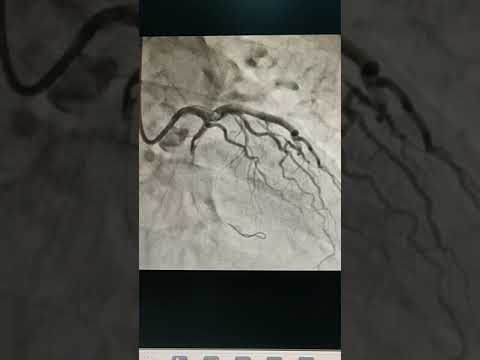

Case 242: Manual of CTO PCI - Sequential guide technique

InWire Guidewire CTO

Difficult PTCA